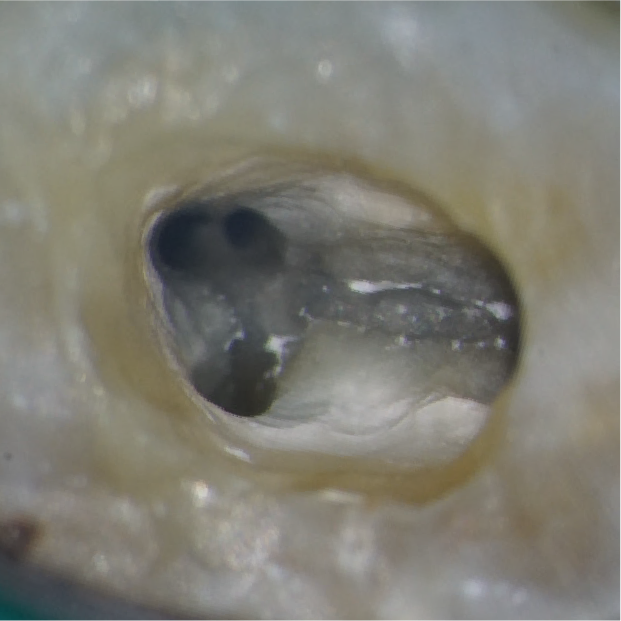

before

矢印の部分には、これまで見つかっていなかった細い根の管(根管)があります。マイクロスコープで大きく拡大して見ることで、わずかな入口を慎重に探し出し、丁寧に開くことができます。

after

その結果、隠れていた根管を安全に見つけ出し、適切な治療を行うことができました。